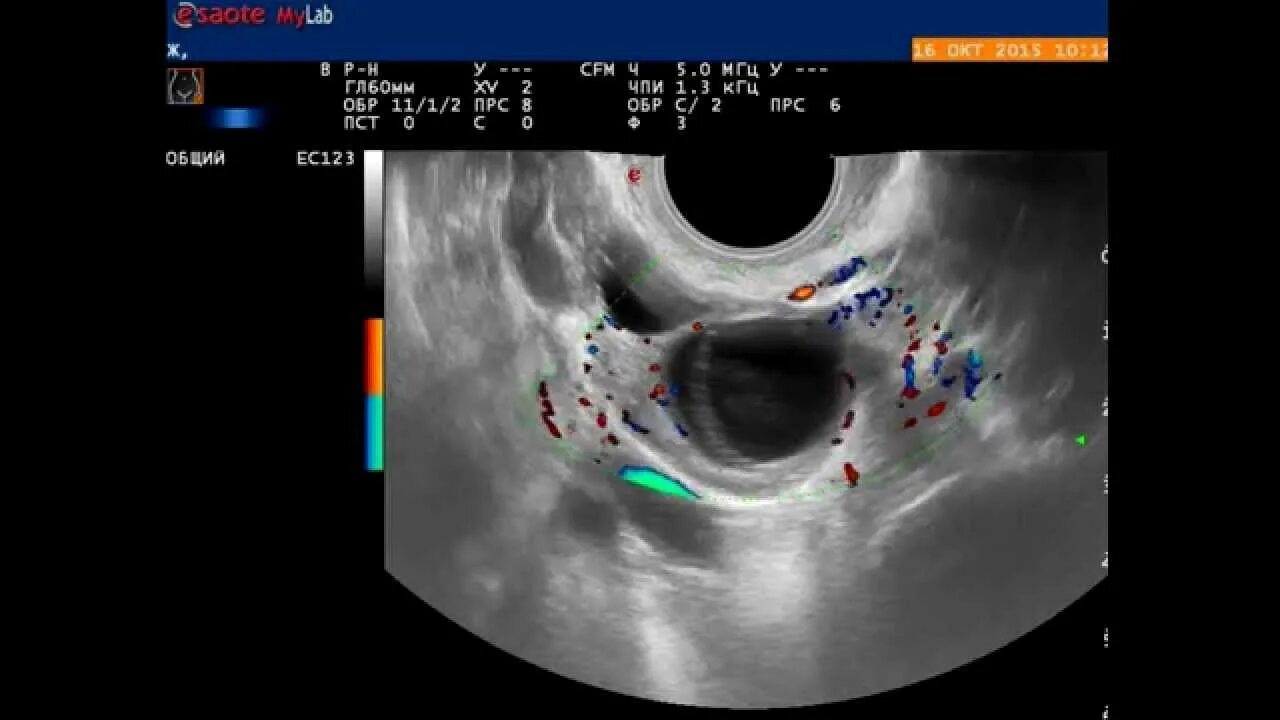

Персистирует фолликул